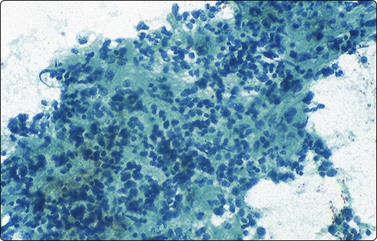

The small non-cleaved cell lymphomas such as Burkitt and non-Burkitt types, usually presents in the nonendemic form with enlargement of abdominal lymph nodes and/or visceral organs.4,45,71 Ovarian involvement may be seen in females. Aspiration smears are highly cellular and demonstrate monotonous population of singly dispersed cells with round nuclei, moderate to high nuclear to cytoplasmic ratios, coarse clumping of chromatin, and prominent nucleoli (Fig. 17.13). Multiple nucleoli are seen in Burkitt-type and single nucleoli are noted in the non-Burkitt type. Nuclear irregularities and polylobated nuclei are often seen. On Romanowsky-stained smears, numerous cytoplasmic vacuoles are seen in Burkitt lymphoma (Fig. 17.14). The vacuoles are due to the accumulation of neutral lipids, which can be stained with oil-red-O. Abundant mitotic figures and apoptosis are seen and are indicative of a tumor with extremely rapid turnover. Phagocytic histiocytes are often seen in the background.

image

Fig. 17.13 Burkitt lymphoma

Aspirates are extremely cellular, containing intermediate-sized, predominantly round nuclei with coarsely clumped chromatin and one or more prominent nucleoli (Papanicolaou, ×200).